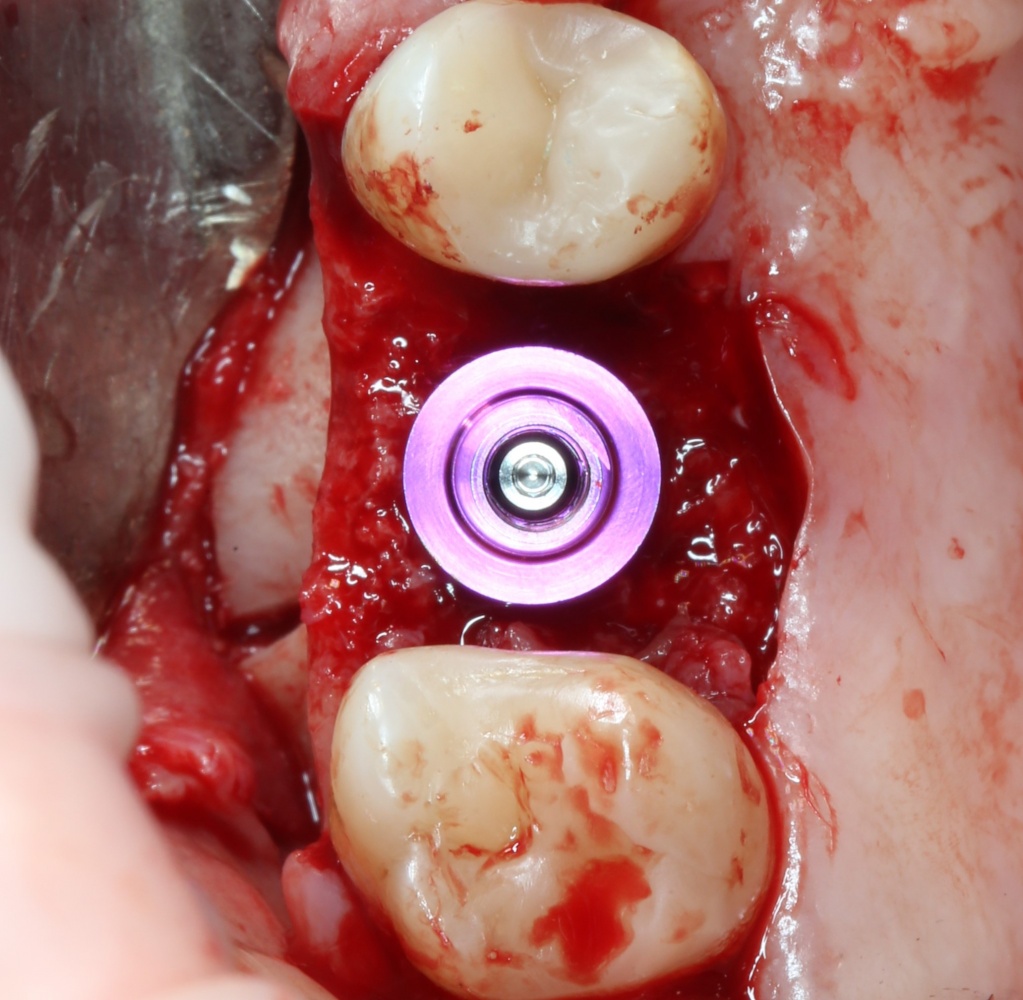

Устанавливаем формирователи десневой манжеты. Сегодня я называю эту процедуру не менее важной, чем любой другой этап имплантологического лечения:

И швы. Просто швы. Никаких дополнительных процедур.

Если честно, то сейчас бы я использовал другой шовный материал и другой тип швов. Одно неизменно, — и я об этом много раз говорил, — самая широкая часть формирователя десны должна находиться на уровне десны. Так, чтобы эффективно отрабатывать т. н. «биологическую ширину».

Через неделю я снял швы, а мой коллега Андрей Карнеев (дело было еще в НИЦ) приступил к изготовлению протезов. На это ушло полторы недели: